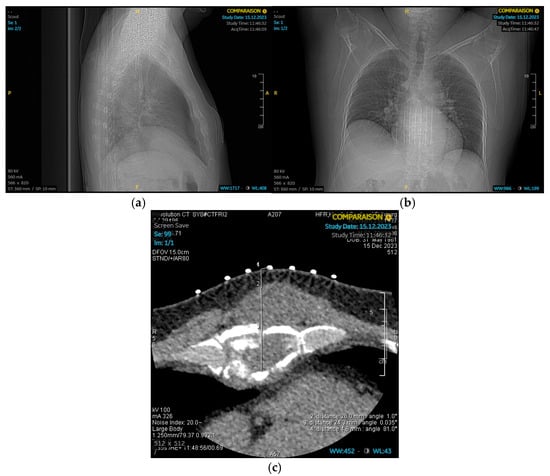

2. Case Presentation

2.1. Patient Background